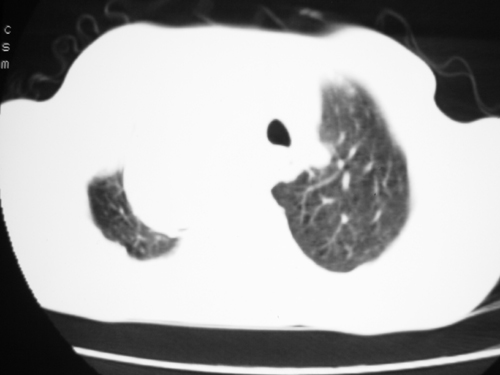

以下是引用yangyudong333在2008-4-29 5:46:00的发言:[br]1左上叶结节呈分叶状,边缘毛刺,考虑肺癌并纵隔淋巴结转移可能性大,结核待排,[br] [br]2右侧多发包裹性胸腔积液

以下是引用zsl6918在2008-4-29 9:15:00的发言:[br]右侧包裹性积液穿刺术后改变,肺内多发结节不除外转移可能。建议查胸水,问病史。